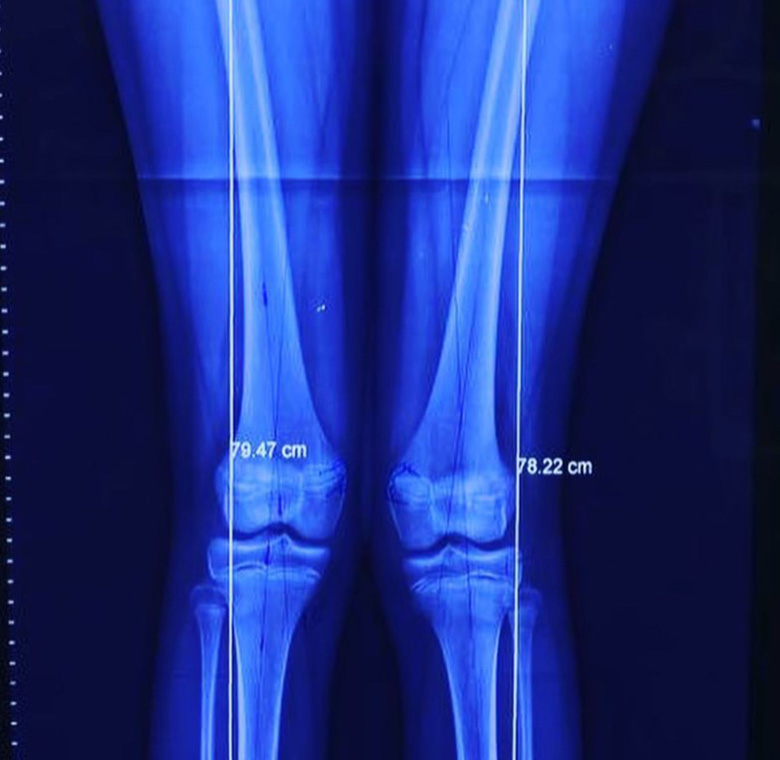

Deformidad rodillas en valgo

Rodillas en valgo

Rodillas en valgo con rótula alta